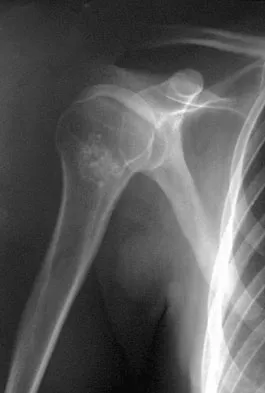

A 40-year-old woman who is an avid tennis player reports the insidious onset of progressive left shoulder pain for the past 2 months. Examination reveals full range of motion with a positive impingement sign. Strength in the supraspinatus and infraspinatus muscles is normal, although stress testing is painful. An earlier subacromial cortisone injection provided good, but only temporary relief. An AP radiograph of the left shoulder is shown in Figure 10. Management should now consist of

The radiograph shows calcific deposits within the substance of the supraspinatus tendon. Patients with this condition are prone to recurrent bouts of acute inflammation in the shoulder. While the response to cortisone injection is often dramatic, repeated injections are not recommended because of injury to the collagen fibers. Good results have been obtained with arthroscopic evacuation of the calcium deposits. In one study, the addition of a subacromial decompression did not improve the results. Jerosch J, Strauss JM, Schmiel S: Arthroscopic treatment of calcific tendinitis of the shoulder. J Shoulder Elbow Surg 1998;7:30-37.